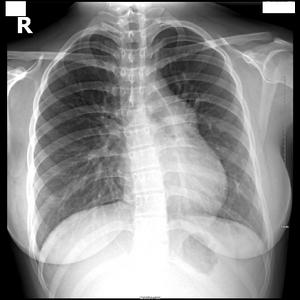

图3-5 肺动脉高压 肺动脉段明显突出